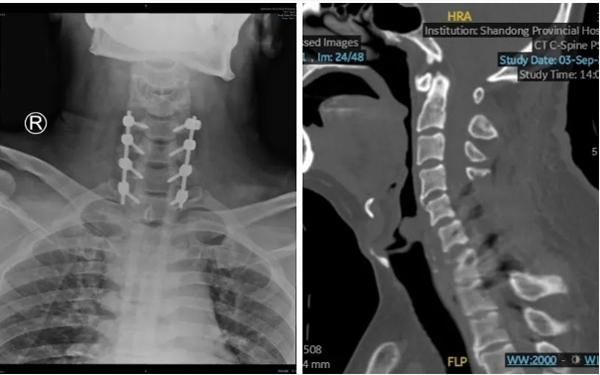

8月29日,创伤中心专家团队为患者实施了一期手术。主任医师张鹏、副主任医师陶扶林与全体医护人员齐心协力,小心翼翼地搬动患者并帮助其翻身。手术采用俯卧位,通过颈椎后路,解除C6/C7关节突绞索状态,恢复正常的颈椎序列。同时,手术全程进行神经电生理监测,确保手术操作不会造成颈髓损伤。术中固定C5-T1脊柱节段,咬除C5-C7椎板,彻底减压,解除颈髓压迫。手术持续3小时,全程在电生理监测下顺利完成,患者颈髓未发生二次损伤,苏醒后肢体活动同术前。

9月11日,创伤中心专家团队为患者实施了二期手术。主任医师周东生、张鹏带领专家团队为患者实施了颈椎前路椎间盘切除减压椎体融合手术。手术采用颈前右侧横切口,暴露定位C6/C7,切除破损椎间盘及C7游离骨块,进行彻底椎管减压。后续植入椎间融合器(Cage),安装前路钛板,进行椎间融合固定。二期手术历时1.5小时,患者苏醒后肢体活动同术前。术后行颈椎CT+三维重建检查显示脱位椎体已经完全复位,颈椎序列良好,脊髓神经功能得到完全保留。